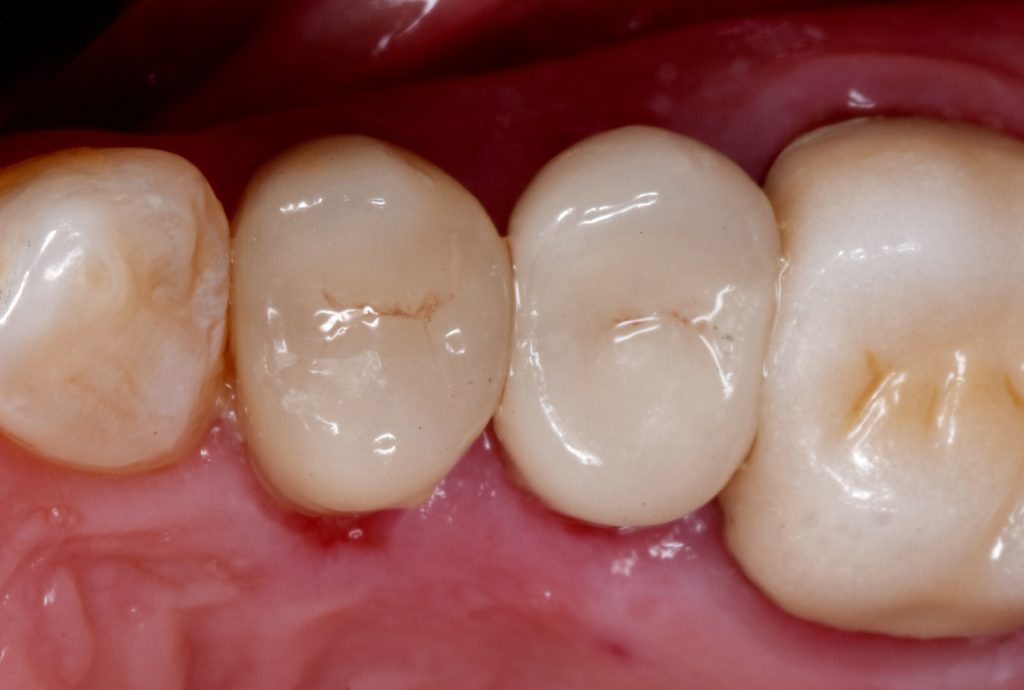

Cementation by heated composite

Shofu beautifill LS